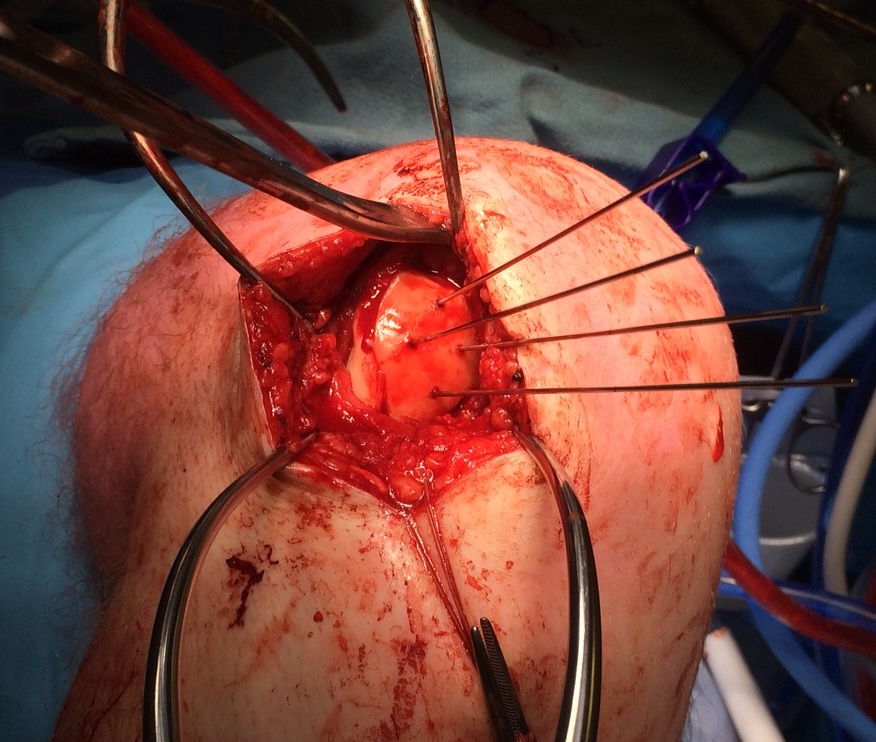

Open bone graft and screw fixation

MFC unstable OCD